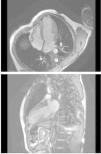

Taquicardia ventricular en paciente joven

L. Hernando Marrupea, R. Cinzaa, R. Porroa, D. Vivasa, N. Gonzaloa, J C. García Rubiraa, I. Vilacostaa

a Servicio de Cardiología. Instituto Cardiovascular. Hospital Clínico San Carlos. Madrid.